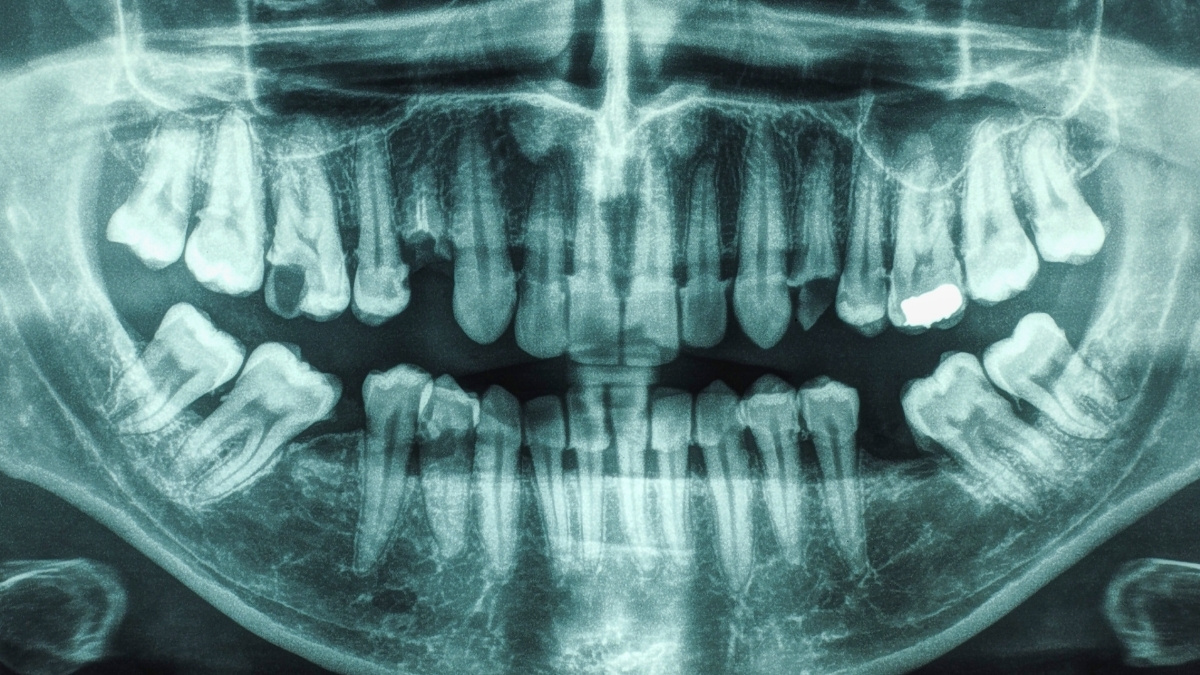

Ambele au fost asociate individual cu accidentul vascular cerebral în trecut, dar puține studii au analizat condițiile în combinație. Astfel, un studiu condus de o echipă de la Universitatea din Carolina de Sud și-a restricționat investigația la persoanele cu afecțiuni de boala parodontală și carii dentare.

„Am descoperit că persoanele care au atât carii, cât și boala parodontală au aproape de două ori mai mare risc de a suferi un accident vascular cerebral comparativ cu persoanele cu o sănătate orală bună, chiar și după controlarea factorilor de risc cardiovascular”, spune Souvik Sen, șeful departamentului de neurologie de la Universitatea din Carolina de Sud.

După ce participanții au fost împărțiți în trei grupuri pe baza sănătății orale bune, a bolii parodontale sau a bolii parodontale și cariilor, cercetătorii au descoperit că doar 4,1% dintre cei cu o sănătate orală bună au avut un eveniment de accident vascular cerebral în trecut. Între cei care aveau doar boala parodontală, procentajul a crescut la 6,9%. În grupul cu boala parodontală și cariile, incidența a fost de 10%.

Odată ce factori comuni contributivi precum indicele de masă corporală și statutul de fumător au fost luați în considerare, calculele finale au arătat că cei cu boala parodontală aveau un risc crescut cu 44% de a suferi un accident vascular cerebral decât cei cu guri sănătoase. Cei cu atât de boala parodontală, cât și cariile aveau un risc crescut cu 86%.